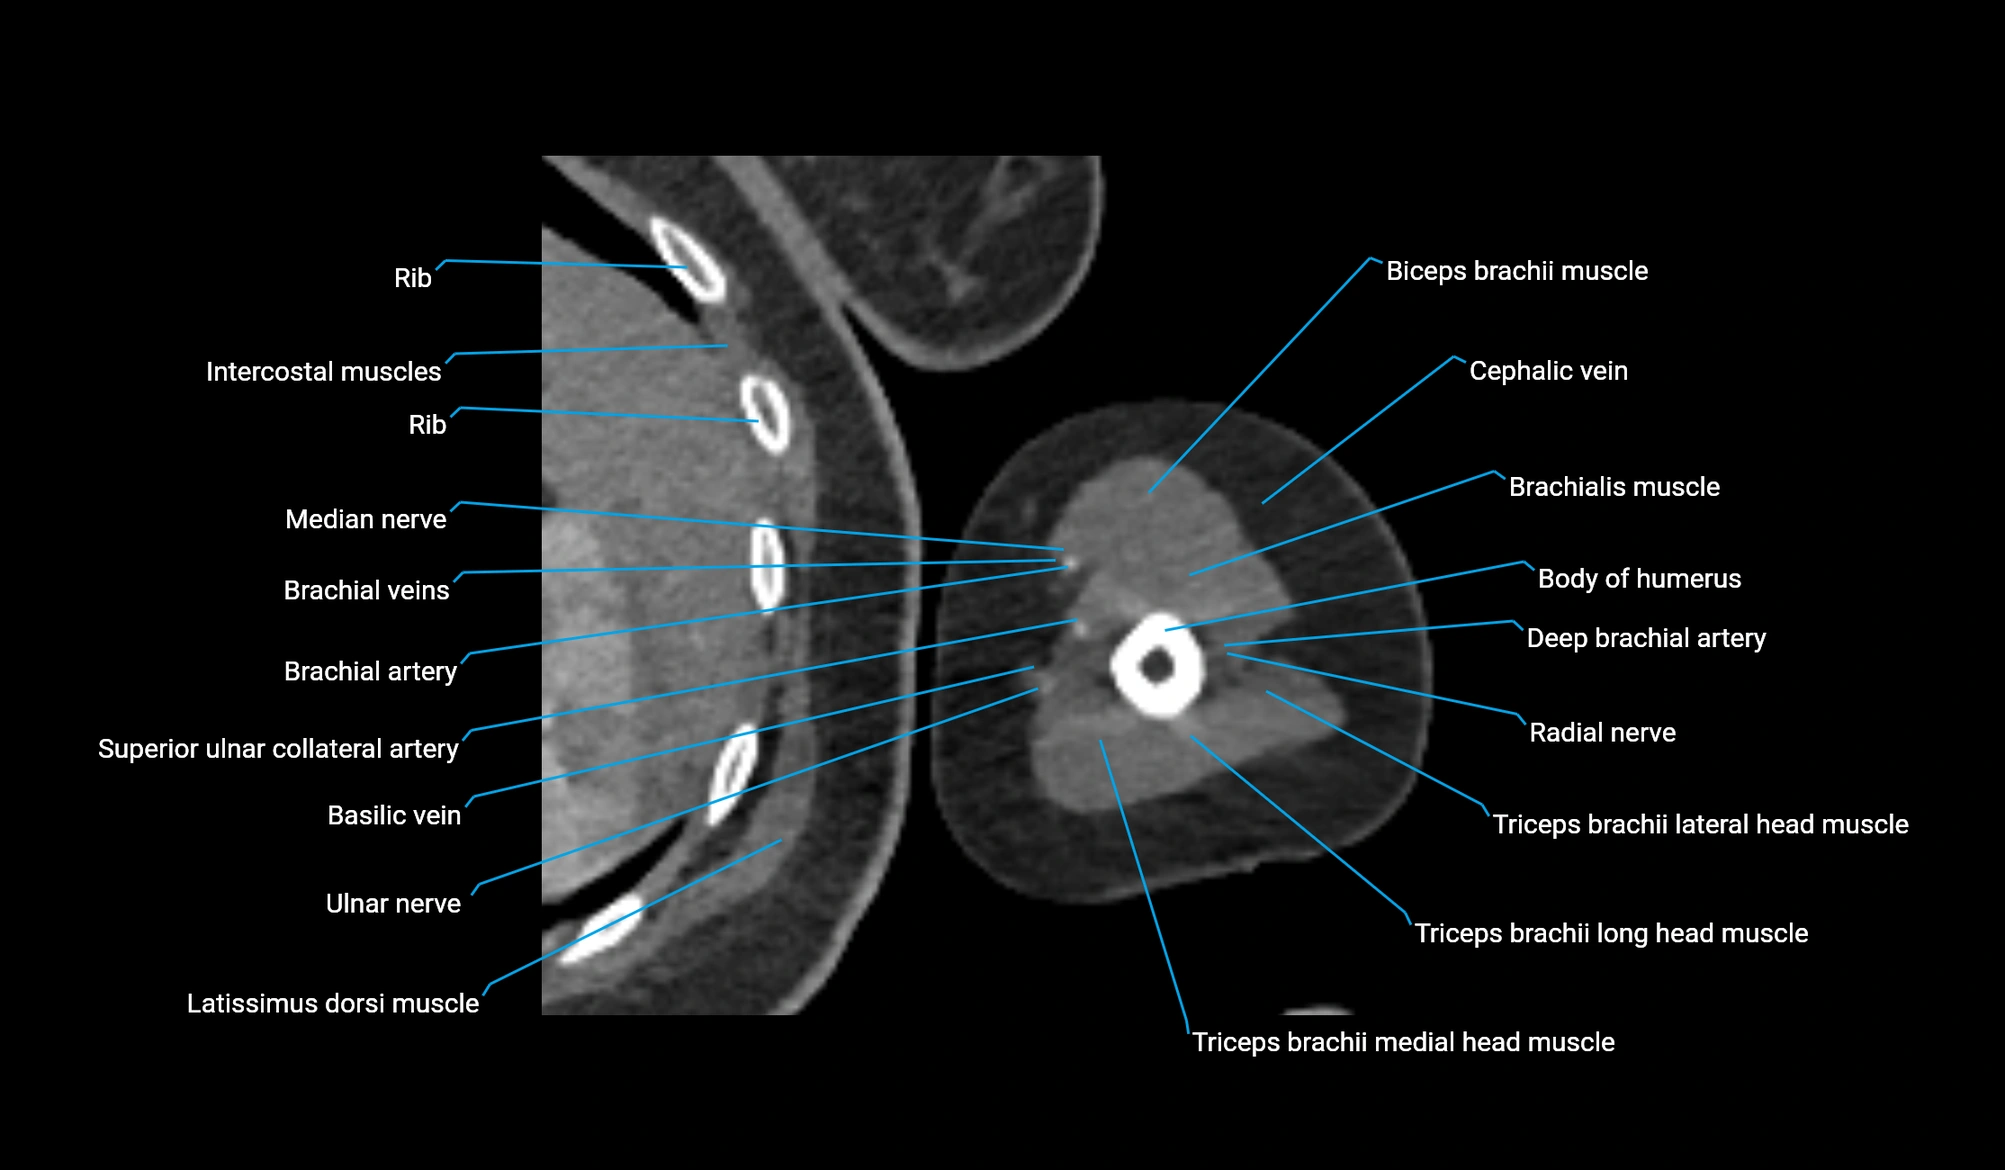

CT image